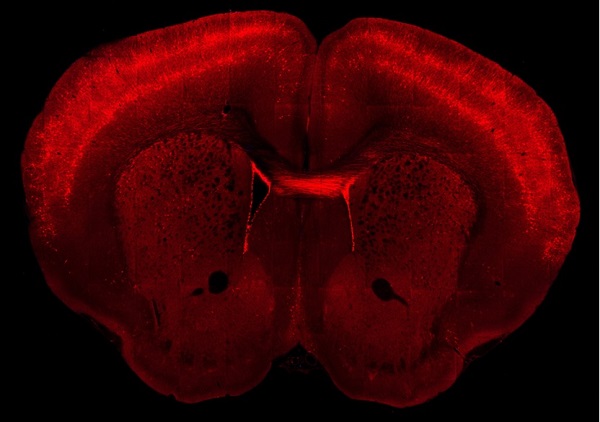

转基因小鼠的脑切片,其大脑皮层中基因定义的神经元用红色荧光标记。

图源:艾伦脑科学研究所